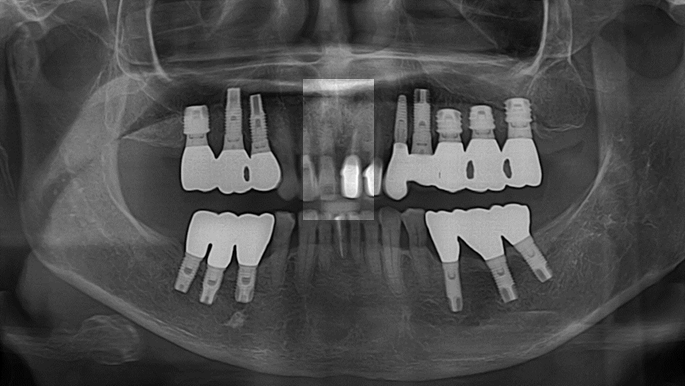

Clinical case: Extraction, immediate placement & loading using

R2GATE solution in aesthetic zone

- Courtesy of Dr. Jong-Cheol Kim, Korea-

Dr. Jong Cheol Kim, immediate loading, digital guided surgery, Digital ONE-DAY Implant, maxillary anterior, #21, guided surgery, immediate loading, AnyRidge, R2GATE, Mega ISQ, MEG Torq, R2GATE Full Surgical Kit

AnyRidge implant system, R2 Guide, R2GATE Full Surgical Kit, Mega ISQ